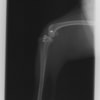

術後左後肢側面像

術後左後肢正面像

術前のTPAは左後肢33.1°右後肢26.8°でしたがTPLO実施により左後肢5.5°右後肢12°に矯正されました。

手術前後のTPA(脛骨高平部の角度)を測定しています。

約29°から約10°へ矯正されています。